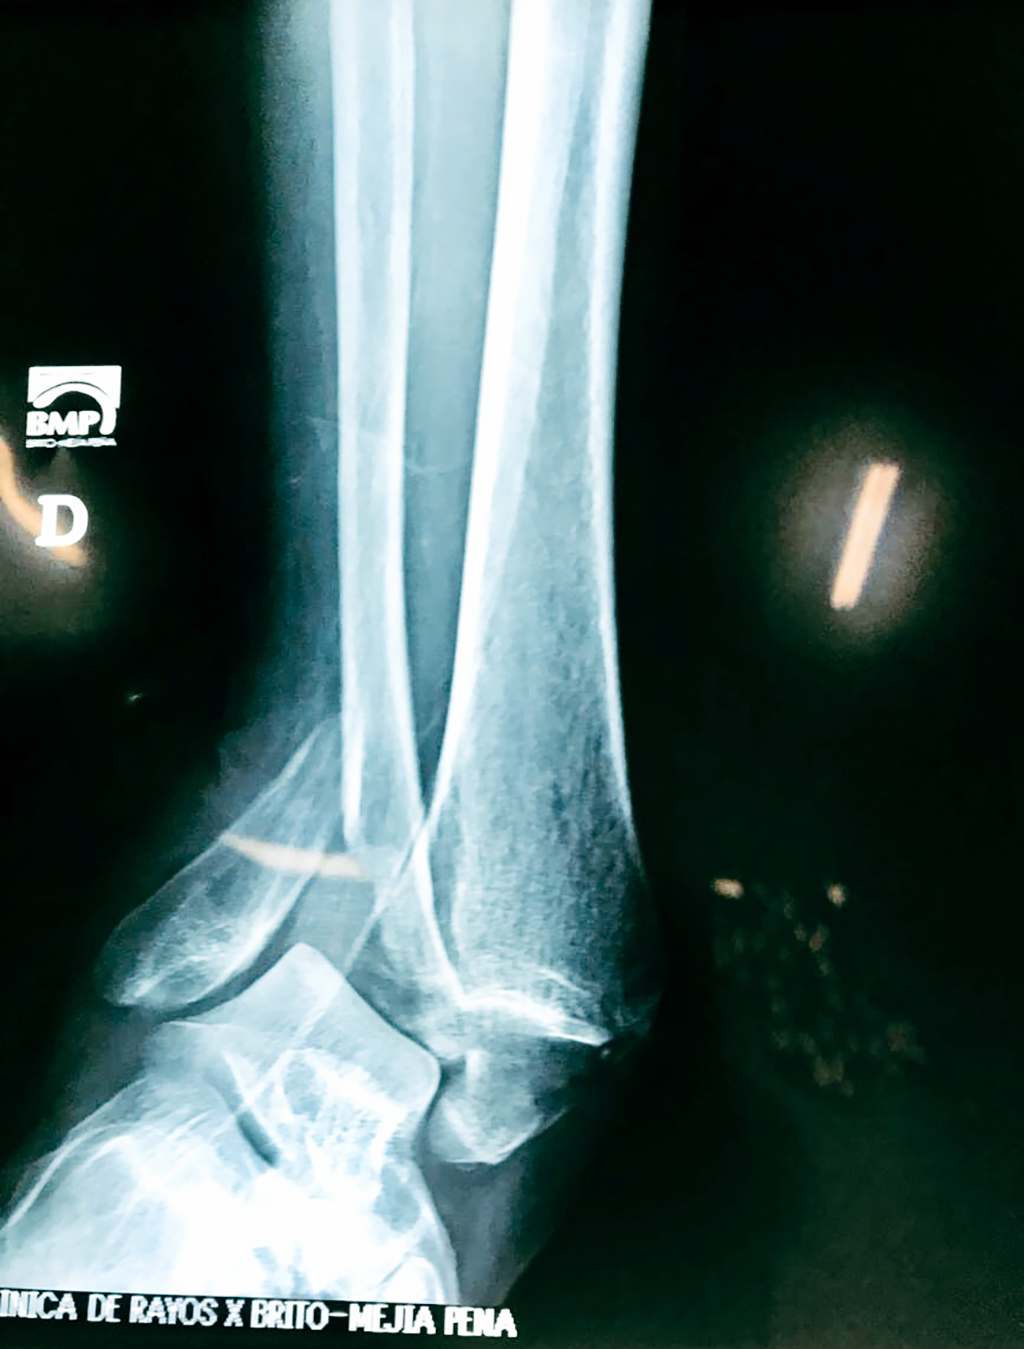

Una fractura de tobillo es la rotura de uno o más de los huesos del tobillo. Estas fracturas pueden ser:

- Los extremos de los huesos están desalineados entre sí (desplazados).

- Los tendones o ligamentos (tejidos que sujetan los músculos y los huesos entre sí) están rotos.